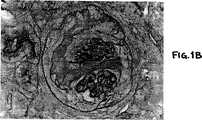

図1A、1Bおよび1C−−マウス腎臓のPAS染色切片の写真である。図1A−−非誘導、非処理マウス。図1B−−GN誘導、PBS(対照)処理マウス。図1C−−GN誘導、抗C5処理マウス。各々の拡大率は同じであり、およそ400倍である。

図2および図5の免疫蛍光染色は、糸球体毛細管ネットワーク(タフト)に閉じこめられており、したがって、図1Bに見られる糸球体の肥大は図2Bおよび5Bにおいては見えない。

図1は、取り囲む間質の中央に位置する単一の糸球体を有するマウス腎臓の切片および各切片の尿細管の横断面を示す。そこに見られるように、GNで誘導し、PBSで処理したマウス(図1B)の腎臓は、炎症性の糸球体過細胞性、明らかな基底膜の肥厚および糸球体の肥大を含む重症の半月体形成性の糸球体の病状を発症したが、一方、GNで誘導し、抗C5で処理した動物の糸球体(図1C)は、非誘導非処理マウスの正常で健康な腎臓の糸球体(図1A)と本質的に区別できなかった。

重度の半月体症状を示す糸球体においては、糸球体毛細管ネットワーク(糸球体タフト(Tuft))のサイズは肥大していないが、上皮細胞およびPAS陽性物質の半月体型の増殖による圧迫の徴候を示し、ボーマンのうが劇的に肥大していることに注意されたい。また、図1Bに示す病的な糸球体の切片においては、過細胞性半月体塊の突出により毛細管ネットワークが二分されていることに注意されたい。

図1Aに示す非誘導非処理マウスの非炎症糸球体は、直径約100μである。図1Bに示すGN誘導、PBS処理マウスの炎症糸球体は、直径約175μである。図1Cに示すGN誘導、抗C5処理マウスの非炎症糸球体は、直径約90μである。